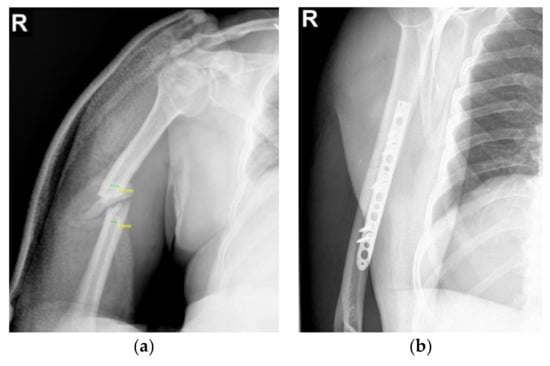

2.1. Clinical Details and Circumstances of Implant Failure